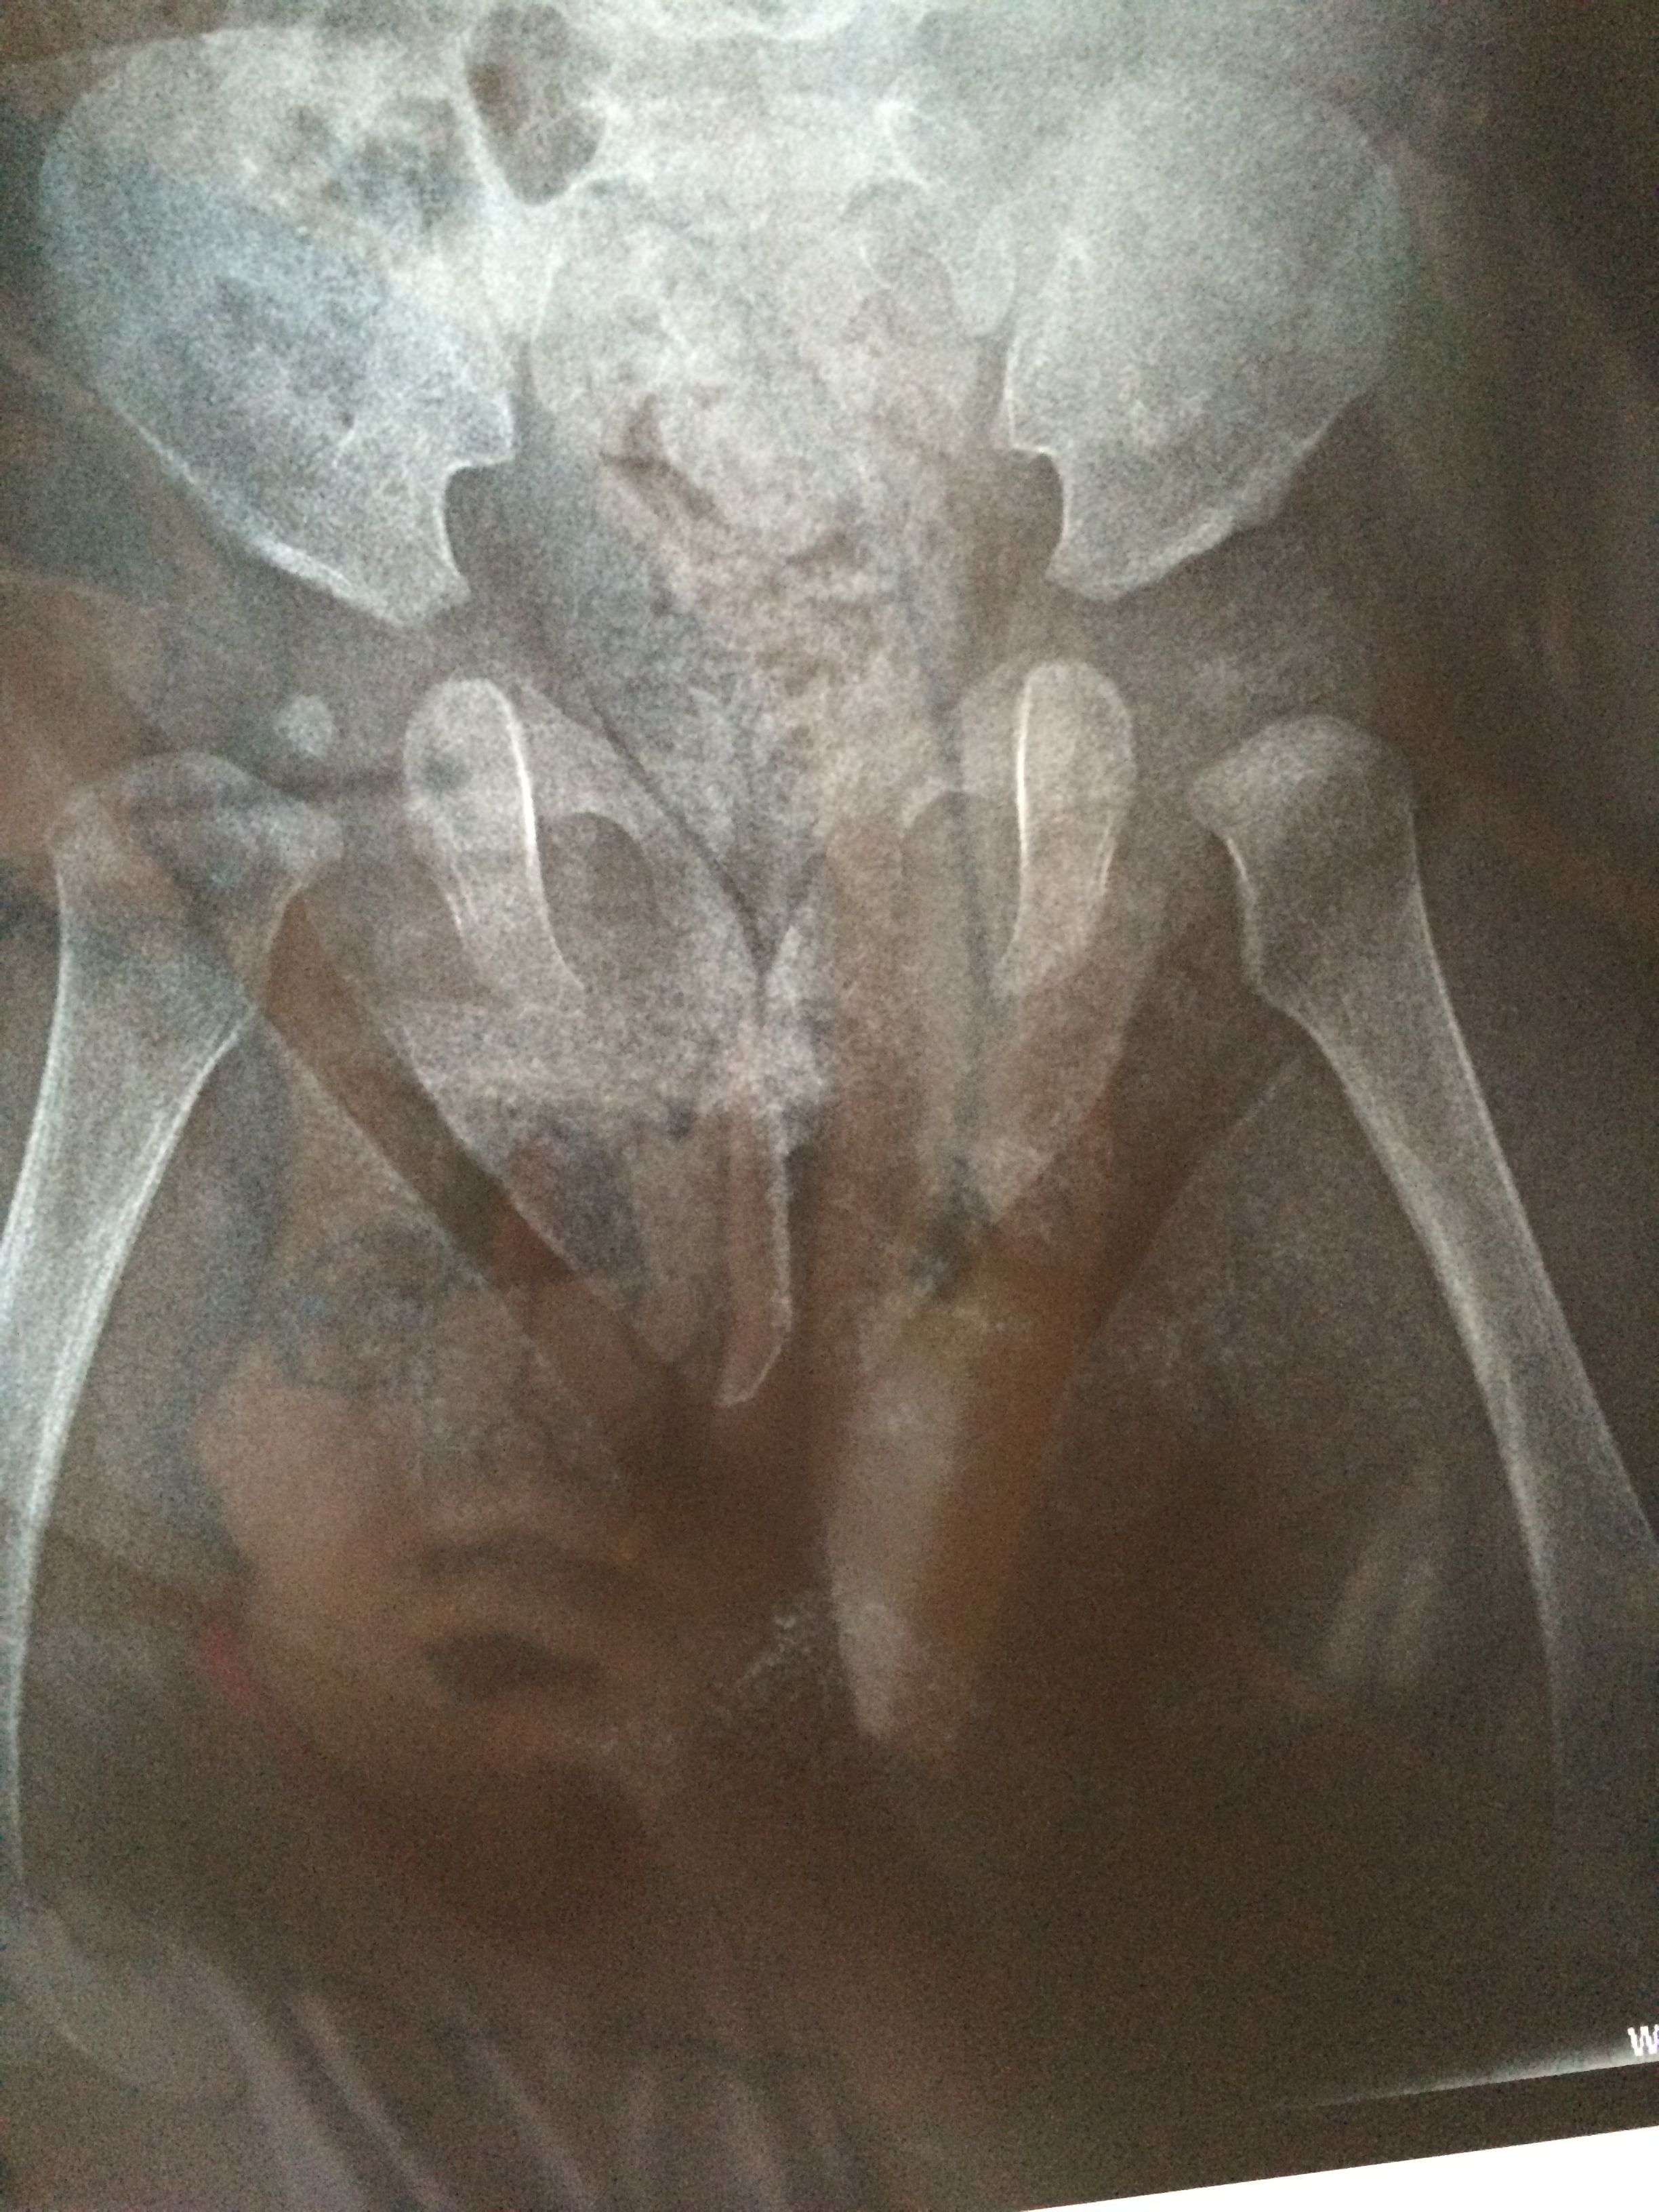

宝宝髋关节发育迟缓(有片),现在戴矫正带,问题大吗 第一张和第二张是4月21号拍的,第三张和第四张是7月7号拍的,骨科医生吩咐说还要带矫正带一个半月,请问如果不戴,髋骨会自己发育好吗?(现在宝宝六个月) 点击展开 匿名用户 2014-07-08 12:43 为您推荐: 其他回答 你好,你这个时候就是要自己注意给宝宝带一些家长气的这样的话只会对宝宝的身体恢复比较好的呢? 可靠的悠闲80 2014-07-08 19:45 相关问题 婴儿髋关节发育迟缓 我的宝宝5个月了 头不能直立 不会自己抓东西 不会吃手 去检查说发育迟缓 该怎么办 两个半月宝宝双侧髋关节发育迟缓角左侧a角56,b角67,右侧a角57 b角64